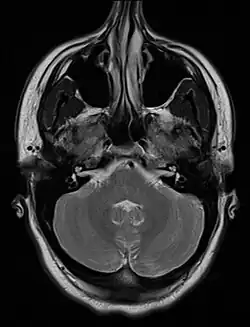

An MRI image showing a congenitally deviated nasal septum, bowed to the left between the eye sockets | |